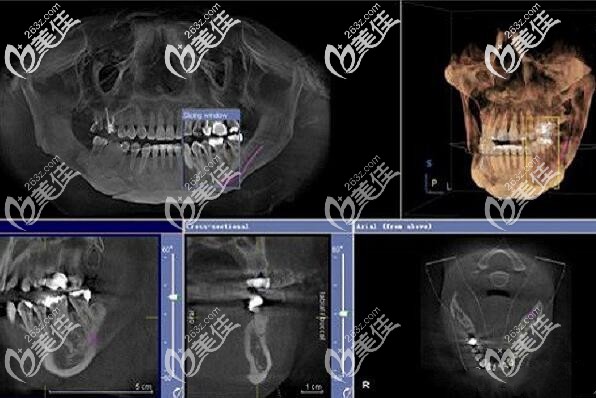

種植牙前的CT片▲

“醫(yī)生說(shuō)自己的牙槽骨萎縮,只有5MM左右,如果做傳統(tǒng)種植牙需要先植骨,也就是說(shuō)多做一次手術(shù),還多花錢(qián);如果做all-on-4全口種植牙,植體可以斜著植入,上下各植入4顆植體就能恢復(fù)全口的咀嚼功能,關(guān)鍵是少受罪、少花錢(qián)、還能當(dāng)天吃東西?!?/p>

這是大叔做完全口種植牙1年后的CT片▲